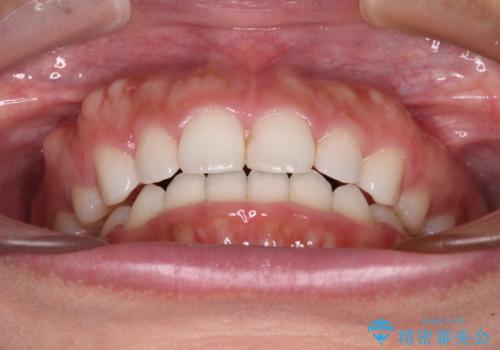

- 口元の突出感を気にして来院された患者様です。

上下左右の第一小臼歯4本を抜歯して口元を下げる治療計画としました。